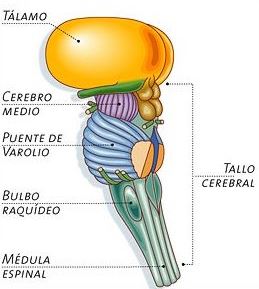

Amb l’entrada d’avui completem els apunts de la unitat 3 d’anatomia sobre el sistema nerviós central. En l’anterior entrada varem veure l’estructura bàsica del SNC i una introducció bàsica sobre les meninges, el líquid cefaloraquidi, l’encèfal, el tronc de l’encèfal i el cerebel.

Se situa entre el tronc encefàlic i el cervell, al voltant del tercer ventricle, el qual el separa en dues regions simètriques. Consta principalment de tres zones ben definides: tàlem, hipotàlem i epitàlem.